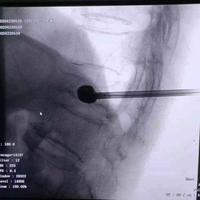

82岁老年女性,胸12椎体骨折。行球囊扩

82岁老年女性,胸12椎体骨折。行球囊扩张椎体成型术...

支架撑开并保留的椎体成型

支架撑开并保留的椎体成型...